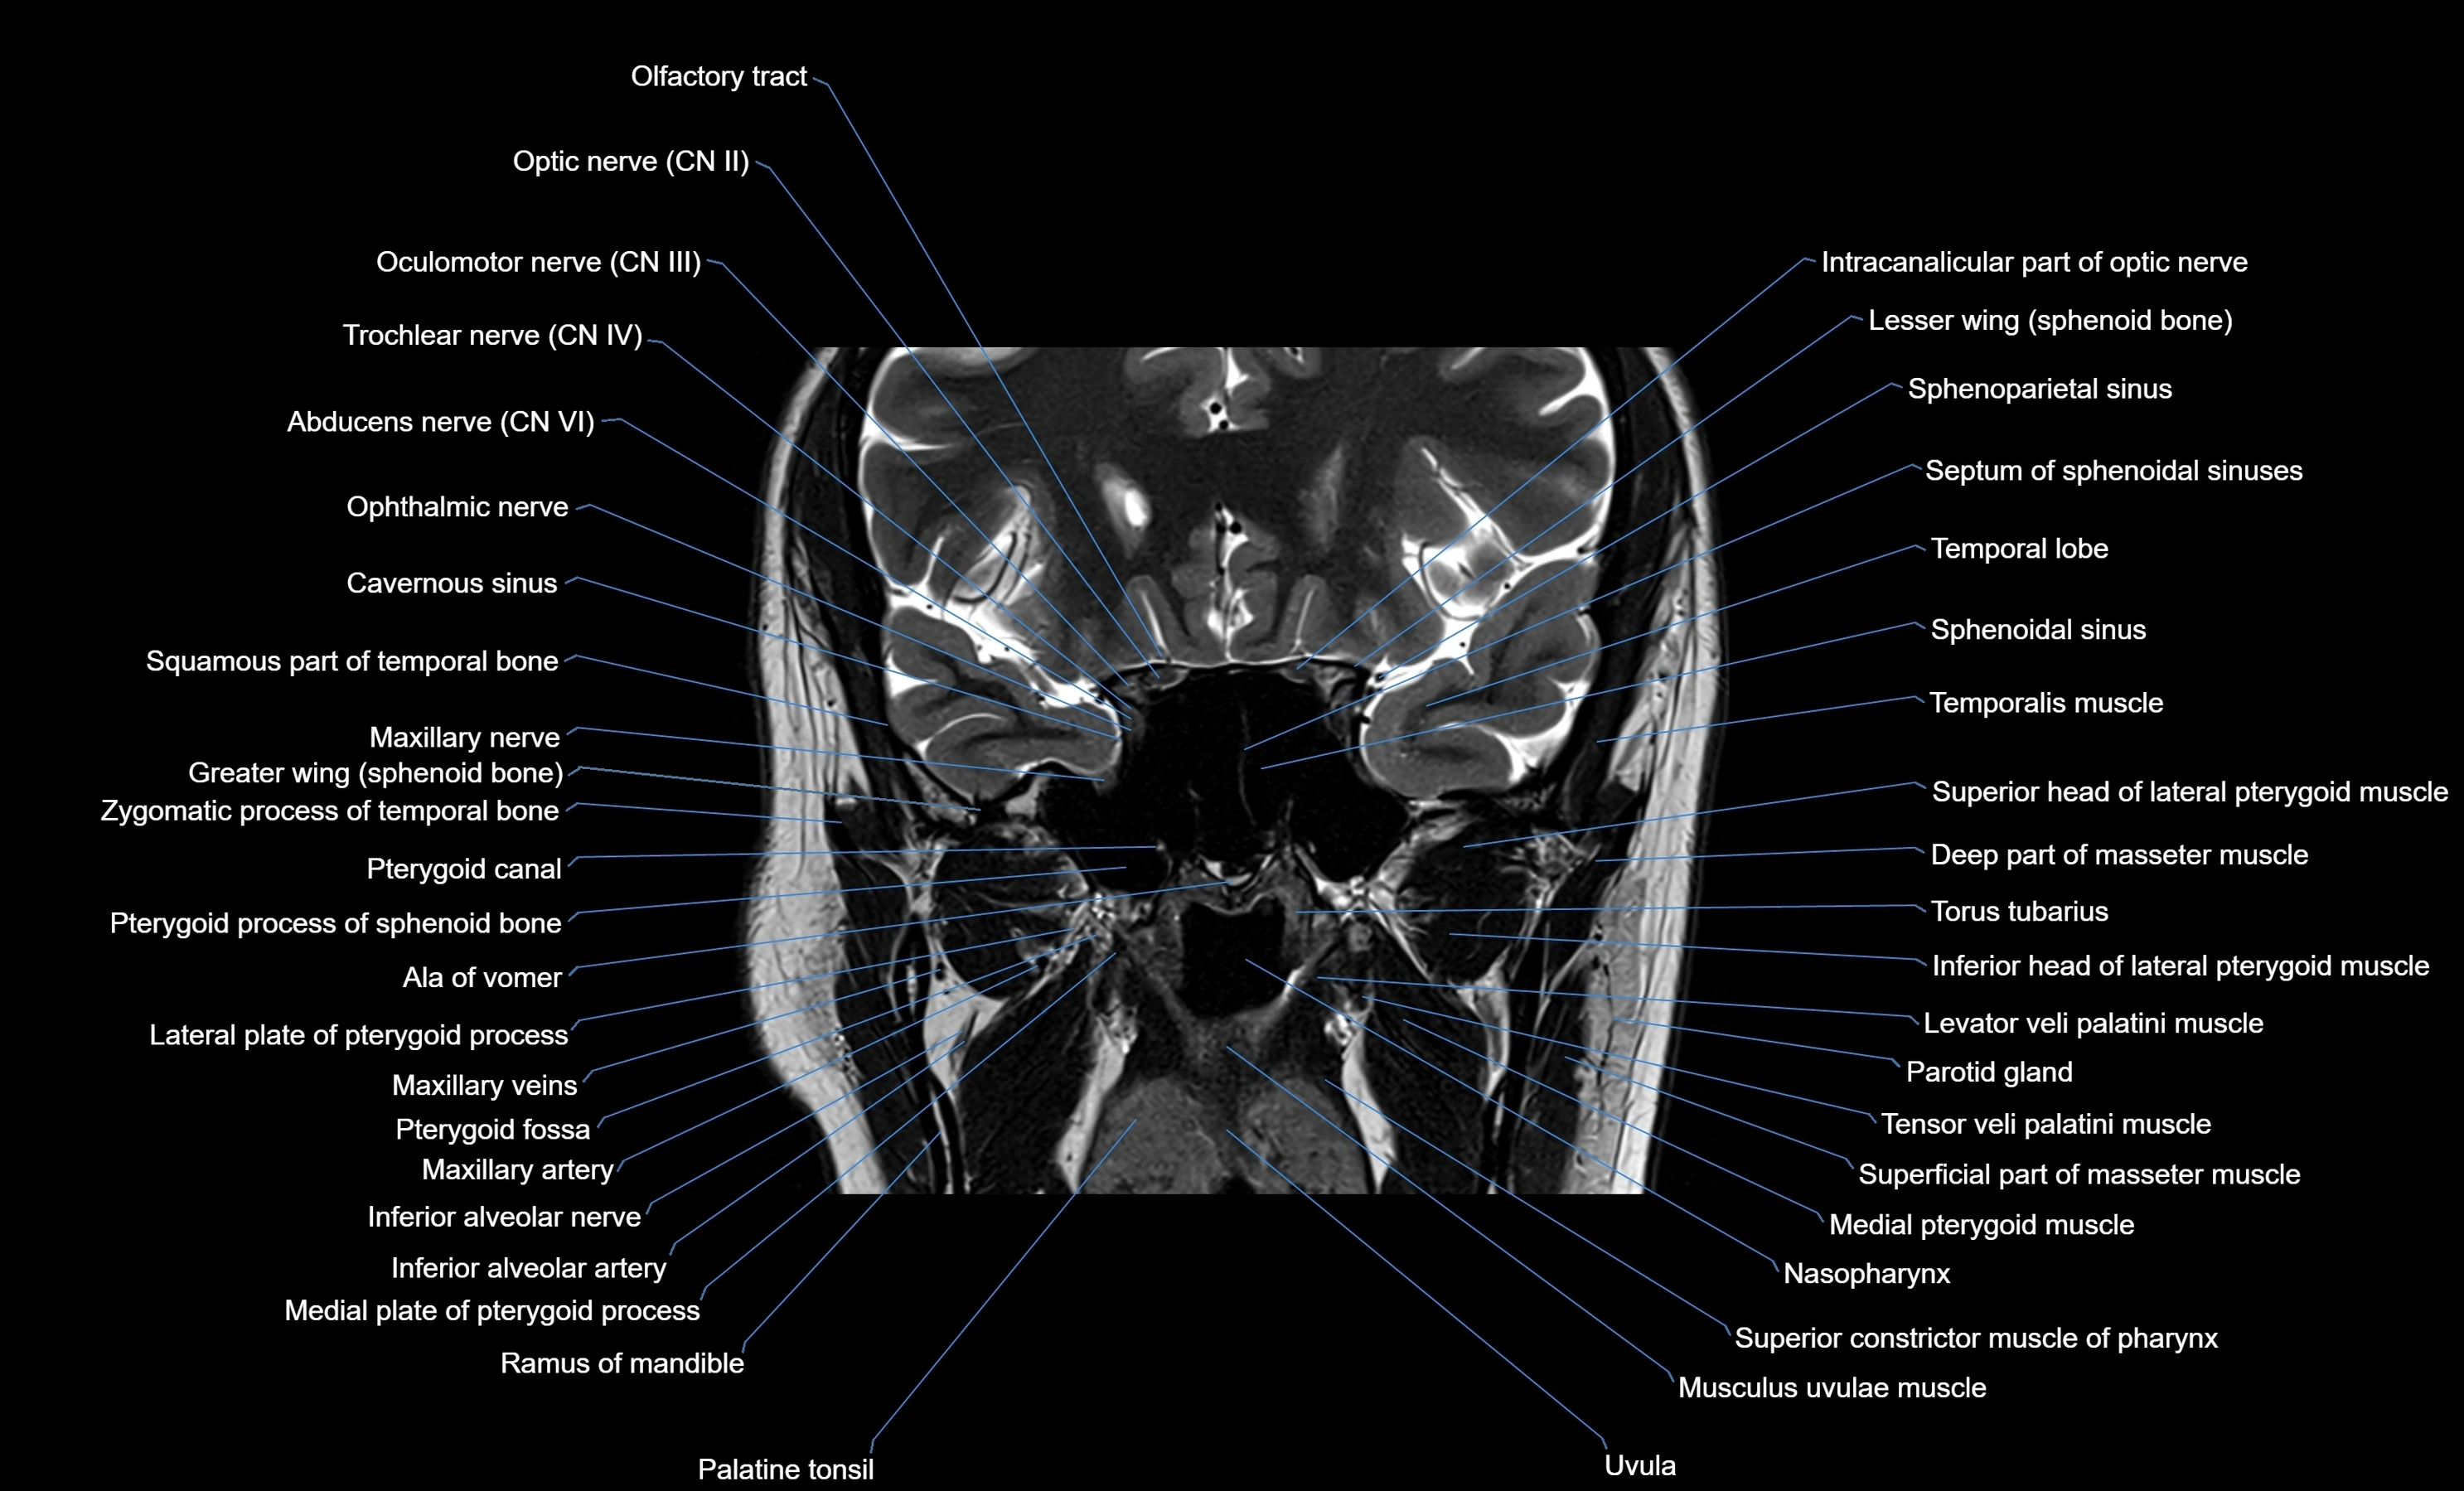

MRI images